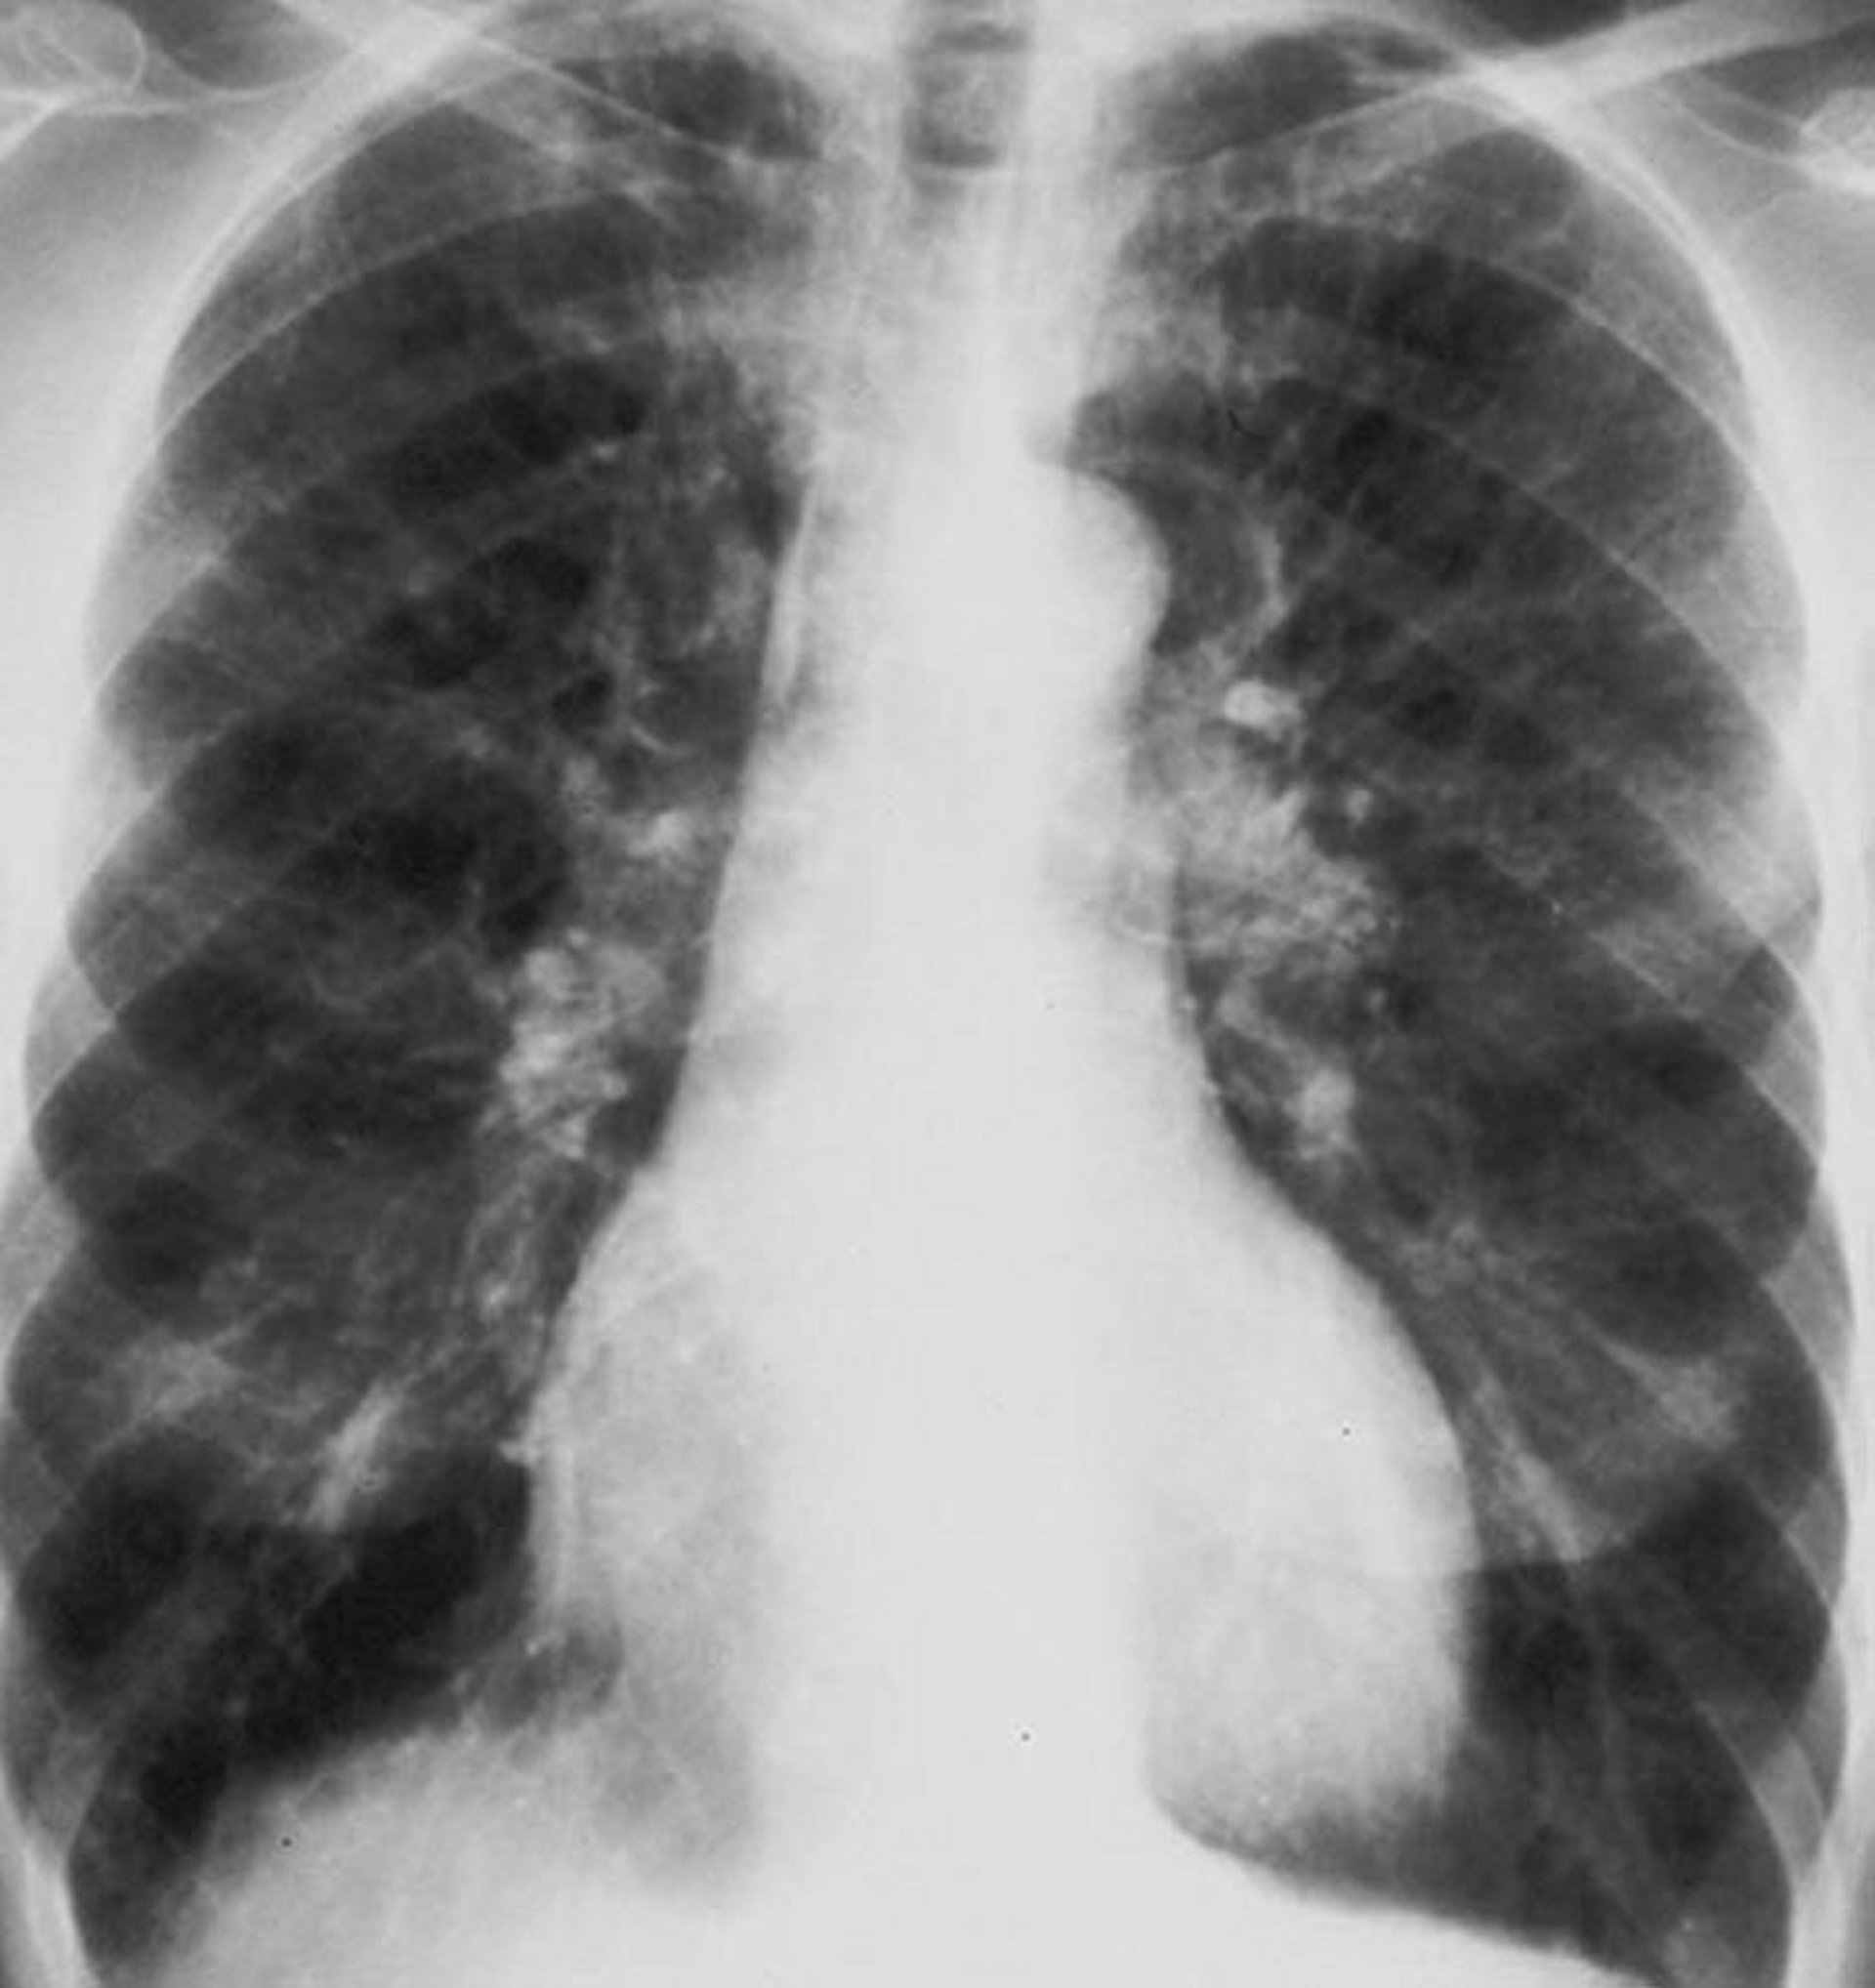

Хроническая обструктивная болезнь легких (рентгенография органов грудной клетки)

Рентгенография органов грудной клетки пациента с хронической обструктивной болезнью легких (ХОБЛ). Присутствует легочная гиперинфляция, диафрагма уплощена, сосудистый рисунок увеличен, а размер сердца незначительно увеличен.

By permission of the publisher. From Barnes P. In Bone's Atlas of Pulmonary and Critical Care Medicine. Edited by J Crapo. Philadelphia, Current Medicine, 2005.